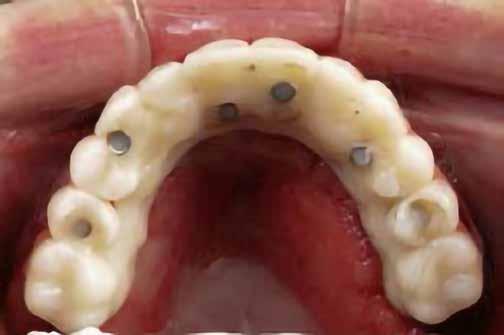

10. ábra: Lágyszövetek a hat hét gyógyulást követően.

11. ábra: Az elkészült híd a szájban – okkluzális nézet.